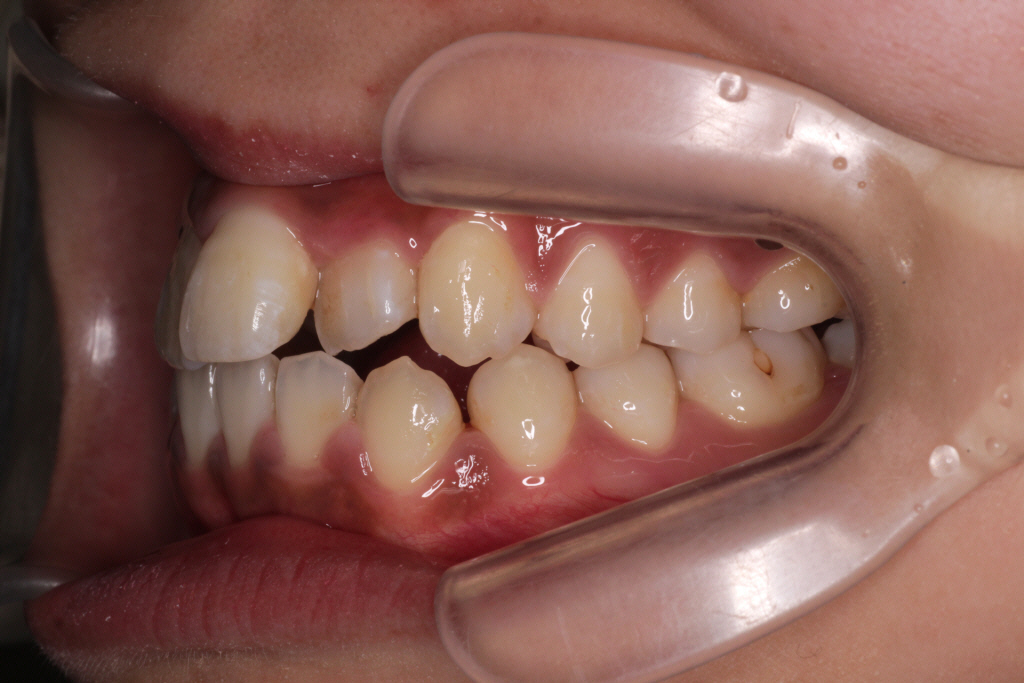

8ヶ月後のお口の中の様子です。↓

様々な理由がありゴムをあまりかけられず、ほとんど動きませんでした。

カリエールモーションはゴムかけしないと、ほとんど意味のない装置です。